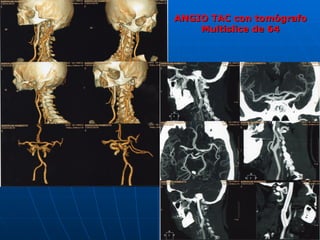

ANGIO TAC con tomógrafo Multislice de 64

ANGIO TAC contomógrafo Multislice de 64